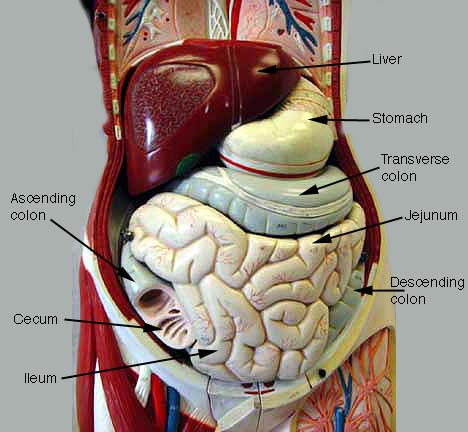

abdomen anatomy model Medically accurate illustration of the abdominal anatomy stock photo

Abdomen Anatomy Model - Vrogue.co

Medically Accurate Illustration Of The Abdominal Anatomy Stock Photo

www.alamy.comabdominal medically accurate

www.alamy.comabdominal medically accurate